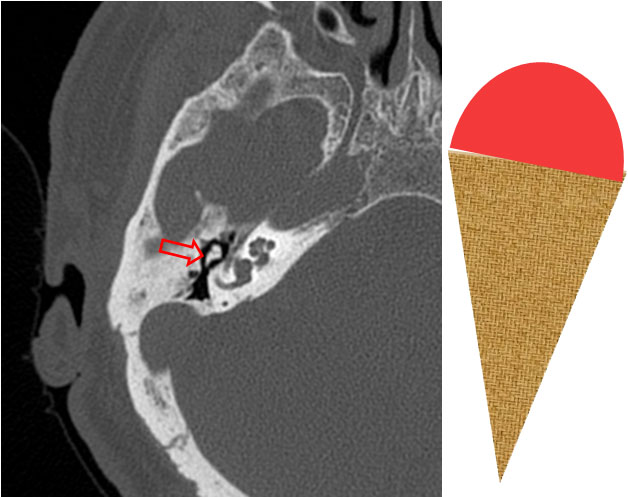

SIGNO DEL CUCURUCHO DE HELADO (en el peñasco normal)

El signo del cucurucho de helado representa el aspecto normal de la articulación entre el yunque y el martillo en la imagen axial de la TC de peñascos. La bola del helado corresponde al martillo y el cucurucho al cuerpo del yunque.

Este hallazgo de normalidad debe buscarse en todos los estudios de peñascos para reconocer la normalidad de la cadena osicular.